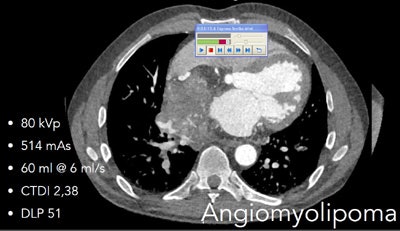

For patients with chest pain, triple-rule-out scans and ECG-gated scans can be acquired rapidly at low radiation doses of 2 mSv or less, and moderate amounts of contrast, usually less than 60 mL. It's possible to "investigate the whole trunk at a max scan speed in cardiac turbo flash mode at 737 mm/sec, a very fast scan mode combined with ECG triggering," he said.